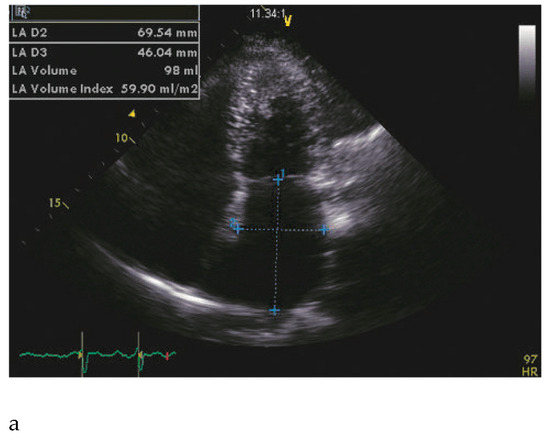

Hypertrophic Nonobstructive Cardiomyopathy as a Cause of Severe Restrictive Physiology

by Stéphane Noble, Caroline Frangos and Philippe L’Allier

66-year-old woman with a family history of hypertrophic cardiomyopathy (HCM) presented with severeprogressive exertional dyspnoea. She had recently complained of palpitations corresponding to atrial fibrillation on the ECG […] Full article

Figure 1